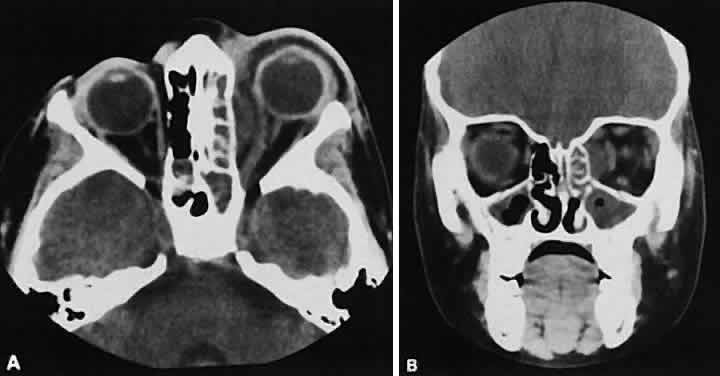

Graves' orbitopathy probably represents the most frequent cause of proptosis and EOM enlargement. The CT findings are fairly stereotyped and typically display various degrees of EOM enlargement (Fig. 7). The inferior rectus muscle usually is affected earliest, followed by the medial rectus, superior rectus, and finally the lateral rectus muscle. Rootman and colleagues13 noted more frequent involvement of the superior rectus/levator and medial rectus muscles than what had been reported previously with Graves' orbitopathy. These muscles can be affected in isolation, with the exception of the lateral rectus. To the best of our knowledge, isolated lateral rectus enlargement has not been reported in Graves' orbitopathy and in our experience usually is associated with a sphenoid wing meningioma.

Fig. 7. Graves' orbitopathy with two variations. Axial (A) and coronal (B) views show symmetric fusiform enlargement of the extraocular muscles with tapered muscle insertions. Note the predominant enlargement of the inferior, medial, and superior rectus muscles with lesser involvement of the lateral rectus muscle, a frequent pattern of enlargement in Graves' orbitopathy. Axial (C) and coronal (D) views of Graves' orbitopathy with expansion of retrobulbar ground substance and relative sparing of the extraocular muscles.

CT evidence of Graves' orbitopathy tends to be bilateral. Approximately 86% of patients with unilateral clinical findings have bilateral CT findings in our experience, which is consistent with the experience of others.42

Morphologically, the EOM belly is enlarged, with a gradual tapering toward and sparing of the tendinous portion of the muscle. Tendon involvement is a typical feature of orbital myositis. Tendon involvement helps to differentiate this lesion from Graves' orbitopathy, although Rootman and Nugent43 have noted a rare patient with Graves' orbitopathy with this finding.